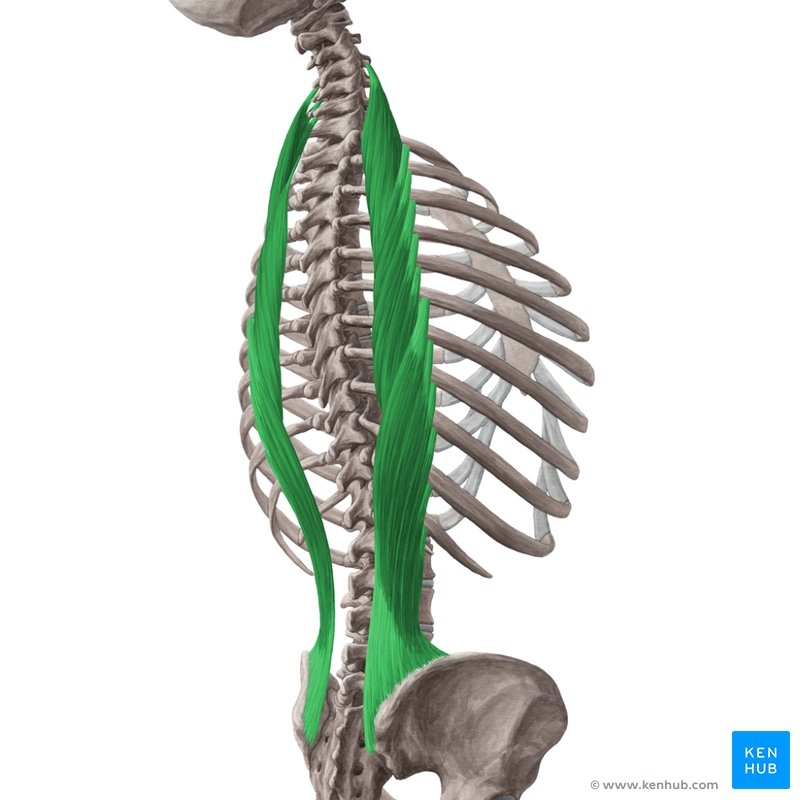

Iliocostalis

Hållning

mm longissimus

Hållning

mm spinalis

Hållning